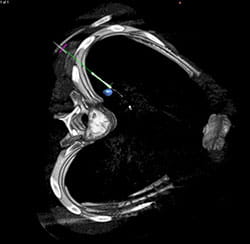

Imaging can be performed in the hybrid OR just before the surgery to help plan the procedure, during the surgery to identify important anatomy or disease, and after the surgery to evaluate results. In some situations, the surgeon will pull up images taken prior to surgery and overlay them with images taken in the hybrid OR. This can provide important details and help improve safety and accuracy.

In addition, the technology can help surgeons see their surgical tools as they navigate them inside the patient’s body. This improves surgical accuracy and helps surgeons avoid critical structures.